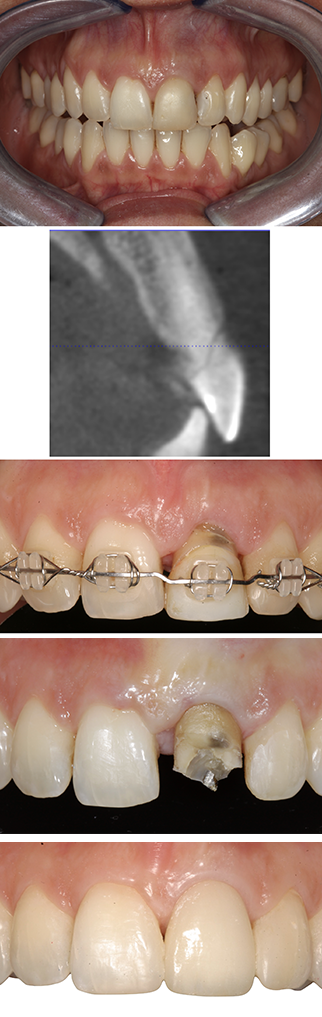

Orthodontic extrusion (see Figure 3), which is also known as forced eruption, represents an alternative or adjunctive approach in the management of teeth with deep subgingival defects. This technique is particularly valuable when surgical crown lengthening would require excessive removal of supporting bone, potentially compromising the periodontal support of adjacent teeth. Forced eruption is especially indicated in cases of root fractures, internal or external root resorption, isolated periodontal defects, or non-restorable teeth in aesthetically sensitive areas. By gradually extruding the tooth coronally, sound tooth structure can be exposed while preserving the alveolar bone and gingival architecture of neighbouring teeth.